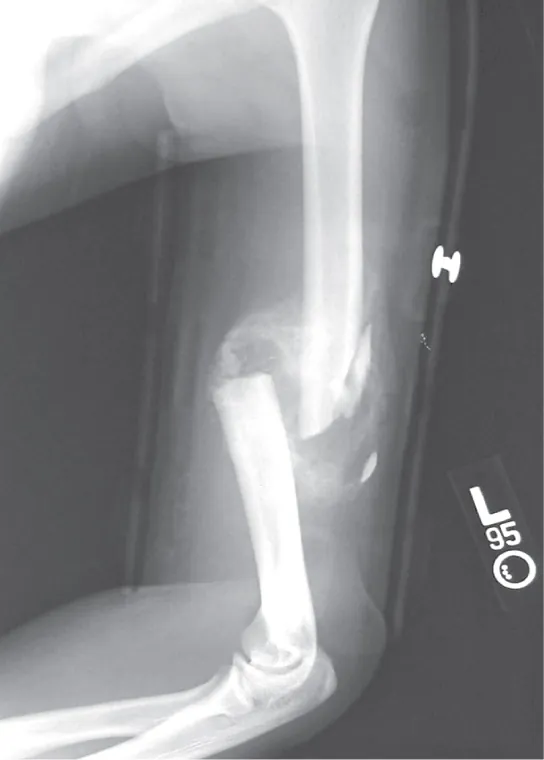

Photo shows an X-ray of a broken humerus—the bone in the upper arm.

Figure 38.22 After this bone is set, a callus will knit the two ends together. (credit: Bill Rhodes)